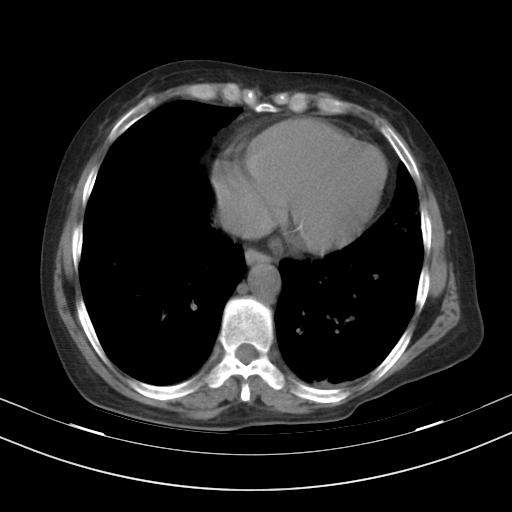

老年女性,嗜睡3天,意识模糊。轻咳,无发热。

1)两肺感染性病变;建议抗炎治疗后复查。2)纵隔淋巴结肿大。3)左侧胸腔积液。

1)先考虑两肺感染性病变;建议抗炎治疗后复查。

2)纵隔淋巴结肿大。

3)左侧胸腔积液。